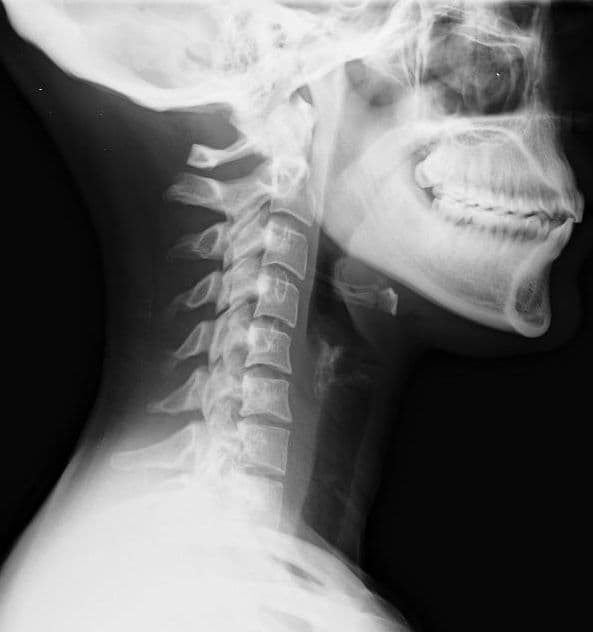

Whiplash is a non-medical term describing a range of injuries to the neck caused by or related to a sudden distortion of the neck associated with extension, although the exact injury mechanisms remain unknown. The term "whiplash" is a colloquialism. "Cervical acceleration–deceleration" (CAD) describes the mechanism of the injury, while the term "whiplash associated disorders" (WAD) describes the subsequent injuries and symptoms. Whiplash is commonly associated with motor vehicle accidents, usually when the vehicle has been hit in the rear; however, the injury can be sustained in many other ways, including headbanging, bungee jumping and falls. It is one of the most frequently claimed injuries on vehicle insurance policies in certain countries; for example, in the United Kingdom 430,000 people made an insurance claim for whiplash in 2007, accounting for 14% of every driver's premium. In the United States, it is estimated that more than 65% of all bodily injury claims are whiplash related, translating to around $8 billion in economic costs per year. Before the invention of the car, whiplash injuries were called "railway spine" as they were noted mostly in connection with train collisions. The first case of severe neck pain arising from a train collision was documented around 1919. The number of whiplash injuries has since risen sharply due to rear-end motor vehicle collisions. Given the wide variety of symptoms associated with whiplash injuries, the Quebec Task Force on Whiplash-Associated Disorders coined the phrase 'Whiplash-Associated Disorders'. While there is broad consensus that acute whiplash is not uncommon, the topic of chronic whiplash is controversial, with studies in at least three countries showing zero to low prevalence, and some academics positing a linkage to financial issues. Symptoms reported by affected people include: pain and aching to the neck and back, referred pain to the shoulders, sensory disturbance (such as pins and needles) to the arms and legs, and headaches.